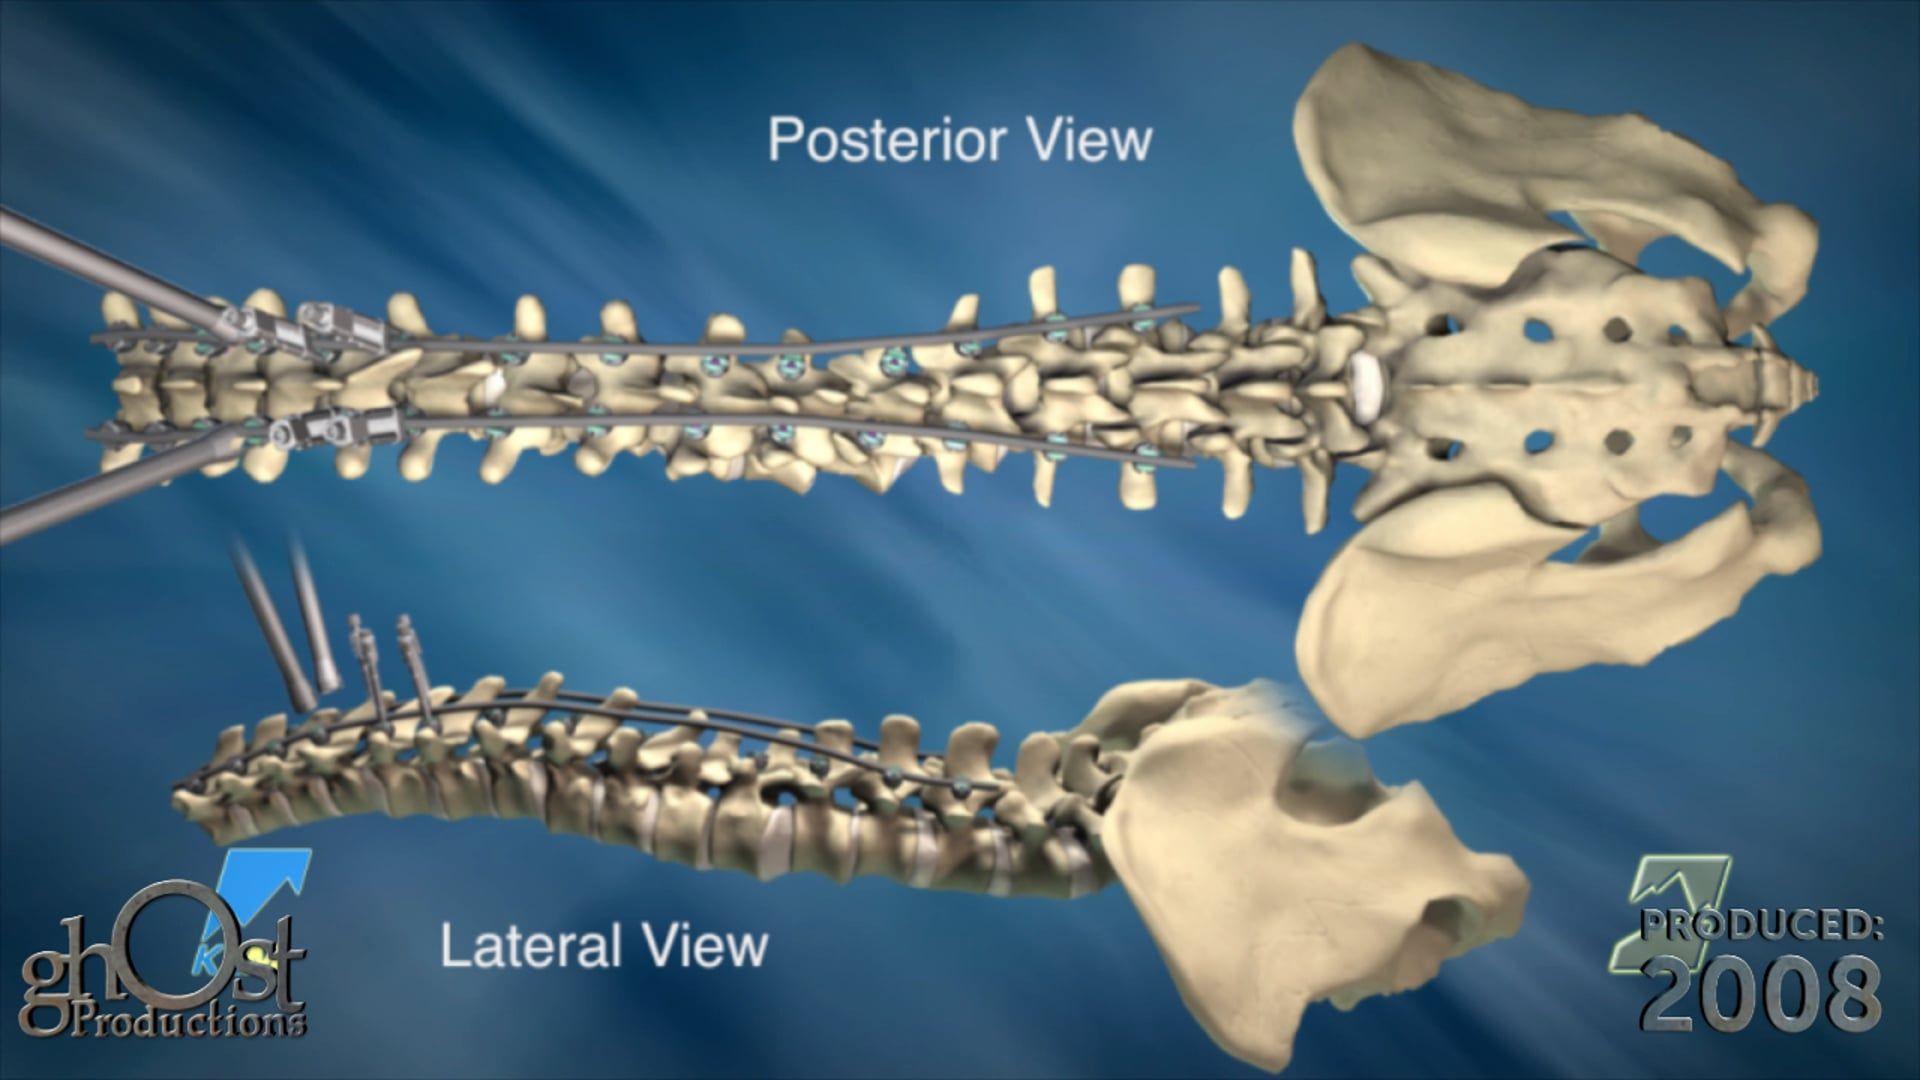

Expanding Orthopedics partners with Ghost Productions to create an animation showcasing their VCF posterior lumbar fixation system for spinal stabilization.

Expanding Orthopedics has collaborated with Ghost Productions to create an informative animation showcasing their VCF posterior lumbar fixation system. This innovative device is designed to stabilize spinal motion and promote interbody bone fusion in patients suffering from vertebral compression fractures. The animation demonstrates how the threaded interbody fusion cage is inserted into the lumbar disc space and used in conjunction with standard pedicle screws to provide optimal support and healing. This video is a valuable resource for medical professionals seeking to learn more about this cutting-edge technology in the field of orthopedics.

Expanding Orthopedics, Ghost Productions, VCF posterior lumbar fixation system, spinal motion stabilization, interbody bone fusion, vertebral compression fractures, threaded interbody fusion cage, lumbar disc space, pedicle screws, optimal support, healing, medical professionals, cutting-edge technology, orthopedics.